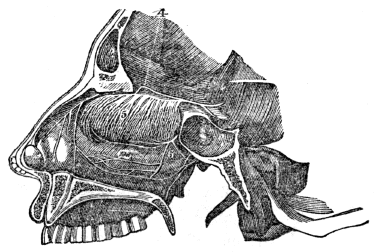

| 43. | Anatomy of the Organs of Smell, | 389 |

| 43. | Physiology of the Organs of Smell, | 391 |

| 44. | Anatomy of the Organs of Vision, | 394 |